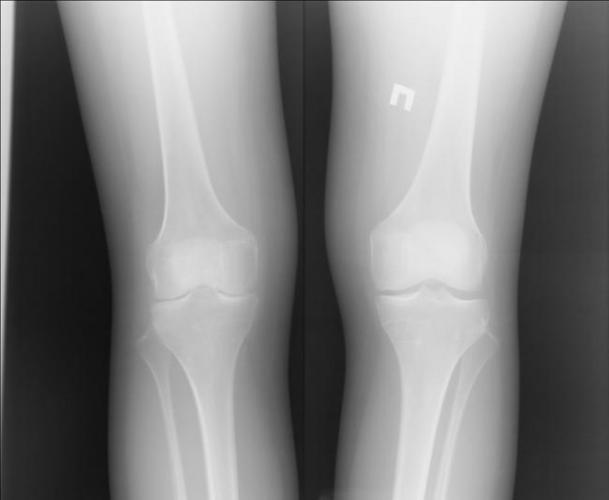

Этапы проведения

Специальной подготовки и длительного времени для проведения процедура не требует. Предварительно колено следует освободить от одежды, чтобы результат обследования был более точным. Если сустав находится в гипсе или на нем повязка, их не снимают. Поза пациента зависит от патологии, чаще всего рентген делают лежа. Иногда врач просит согнуть ногу в колене. Некоторые случаи требуют сравнения больного сустава со здоровым, поэтому делаются снимки обеих ног.

Рентген коленного сустава в двух проекциях — прямой и боковой, дает более полную и объективную картину. В этом случае врач может оценить состояние суставного сочленения со всех сторон. Сначала снимок попадает в руки к рентгенологу, который его расшифровывает и дает письменное заключение результатов обследования. После этого лечащим врачом ставится диагноз.

Артроз на рентгеновском снимке отображен в двух проекциях:

- Прямая.

- Боковая.

При выполнении диагностики нужно найти просвет межсуставной щели. А чтобы достичь лучшего качества снимка, луч следует направить перпендикулярно столу с пациентом. Для получения точных результатов сустав нужно разместить в разогнутом состоянии. Дело в том, что при загибании конечностей контуры могут искажаться. Изучая снимок, который был сделан при полном разгибании, можно рассмотреть актуальное состояние суставной щели в разных проекциях.

Помимо прямой проекции, выполняется боковой рентген, который подает луч под уклоном в 10 градусов. Подобный подход отображает структуру отдаленных задних участков суставов.